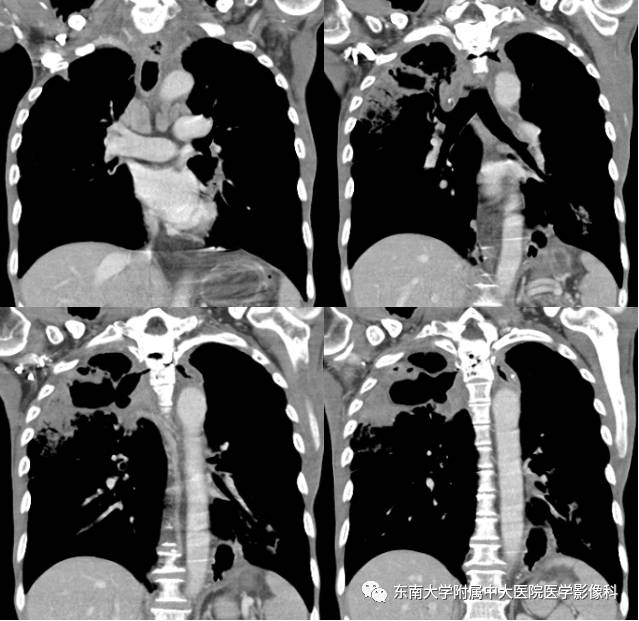

男,60岁,因“食管癌术后5年余,进食呛咳10天”入院。

影像学表现